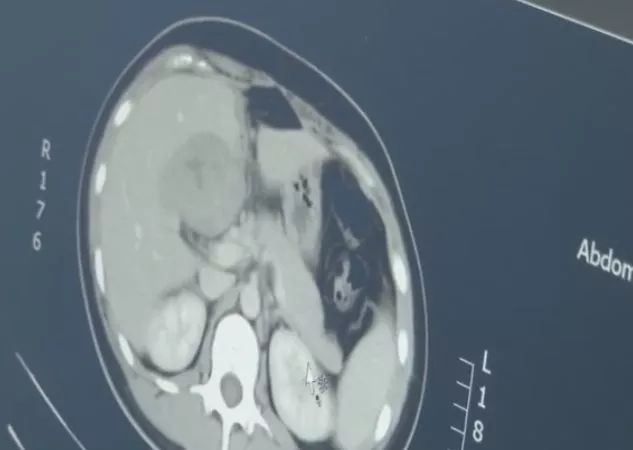

4月22日,安徽天长的尤女士,因为上腹部不适到医院检查,医生在其肝脏部位发现了一个包块,而这个包块不是什么肿瘤,竟然是一个胚胎。

有明显的怀孕指征却找不到孕囊,医生怀疑出现了宫外孕,于是为患者做了CT检查,结果发现,这是一个罕见的宫外孕病例,胚胎跑到了肝脏部位。

据介绍,宫外孕常见于输卵管附近,胚胎跑到肝脏部位极为罕见,很容易引发大出血,危及生命。